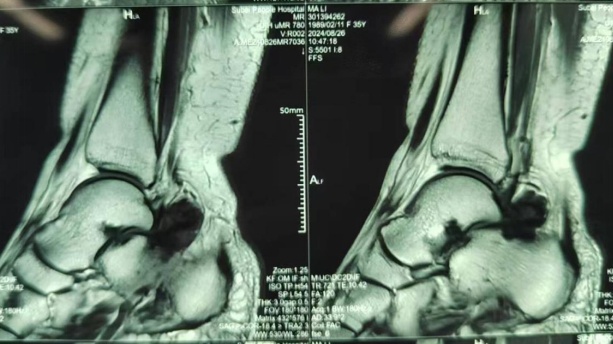

大家可能都注意到,大闸蟹的蟹钳上有着细密的绒毛,不过就在几天前,上海市第六人民医院金山分院骨科收治了这样一位患者:她的踝关节腔内居然和大闸蟹的蟹钳一样长满绒毛!经医生判断,考虑为左踝关节色素沉着绒毛结节性滑膜炎。

医生介绍,这多与创伤有关,多发于年轻人群,男女发病率基本相当,在足踝的发病率约2%-10%,其特点常为单关节受累,临床症状不典型,多为足踝关节部位疼痛不适感、肿胀或积液、活动受限等非特异性症状。

医生建议,色素沉着绒毛结节性滑膜炎有多种治疗方案,手术治疗是首选,其可以彻底切除滑膜增厚组织,尤其是关节镜微创技术,以最小的创伤获得最大治疗效果,术后结合药物、放射等疗法,可取得优良效果,降低复发率。